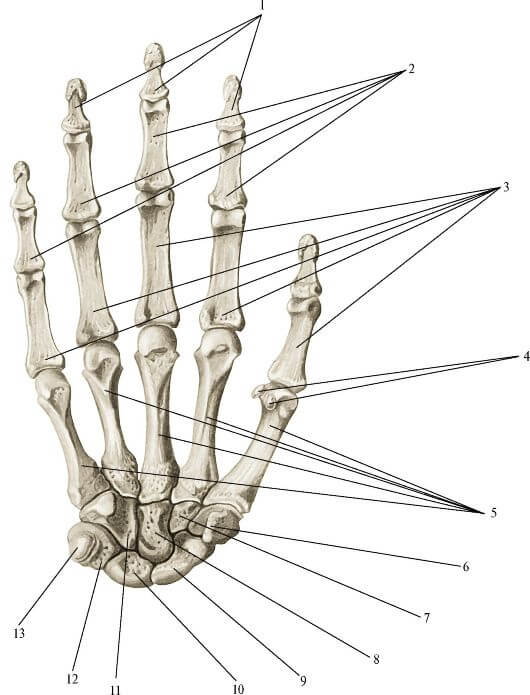

Анатомия кисти руки и строение костей